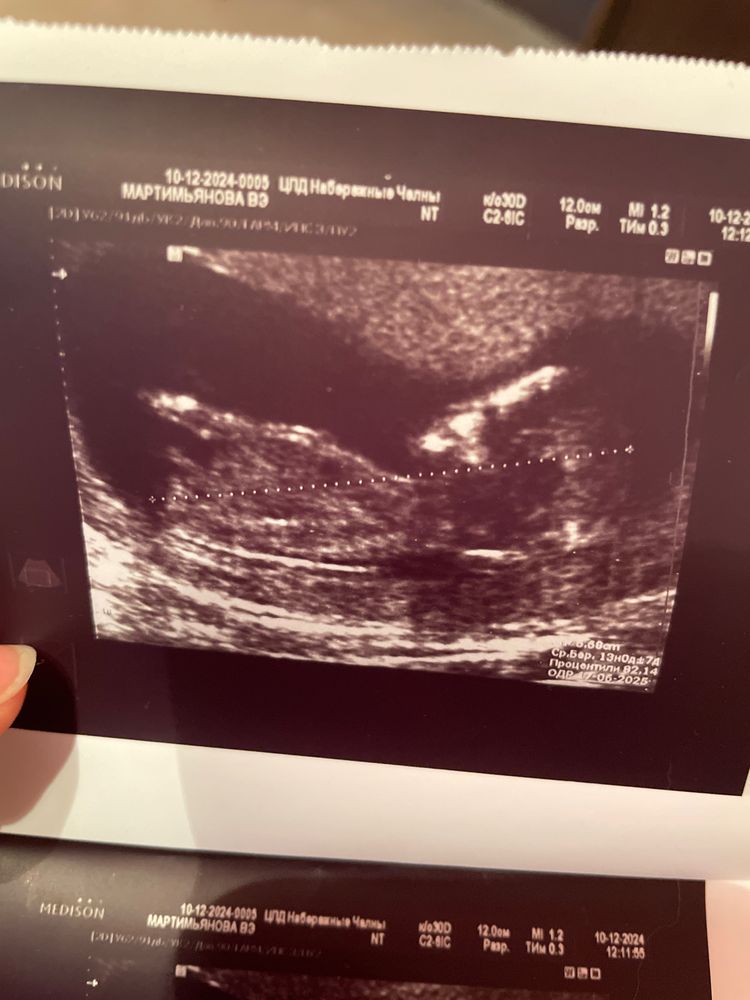

Вот с младшей дочкой. Аппарат вроде хороший.